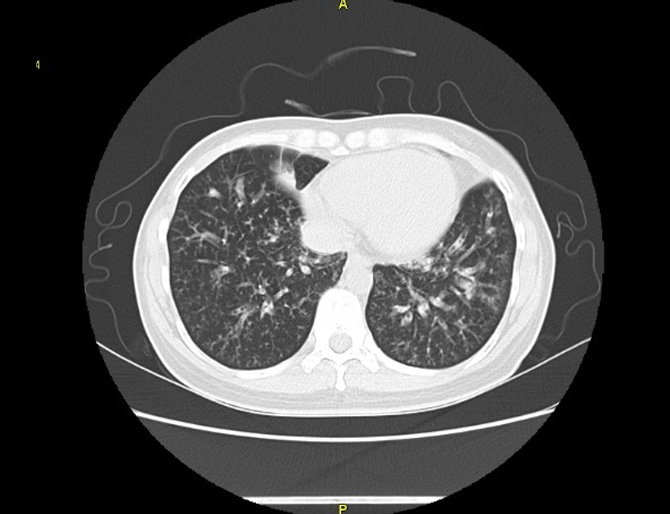

기관지확장증의 CT 사진

​기관지벽의 근육 및 탄력 성분의 파괴로 인해 기관지가 비정상적으로 늘어나 여러가지 문제를 일으키는 질환을 말합니다.

확장된 기관지 내부에는 가래가 고이게 되는데 기관지가 손상되어 있는 상황이므로 잘 빠져나가지 못하게 되고 이로 인해 쉽게 감염되고 그러면서 기관지 벽이 약해집니다. 이렇게 되면 기관지가 쉽게 파괴되고 다시 가래가 증가되는 악순환이 형성됩니다.